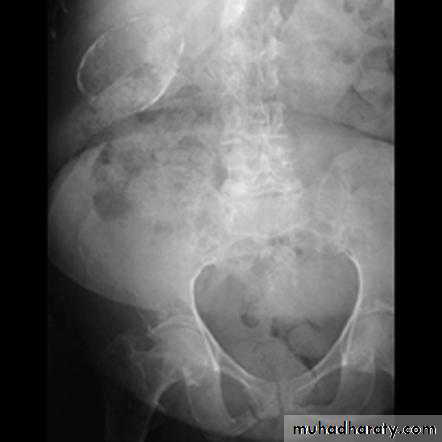

Dilatation of the bowel

Dilatation of the bowel is the cardinal plain film sign of intestinal obstruction

If the bowel is dilated it is important to try and decide which portion is involved

Small bowel obstruction

• Mechanical SB obstruction : small bowel dilation with normal or reduced caliber of colon• Mechanical LB obstruction: dilated colon down to the point of obstruction. May be accompanied by small bowel dilation if the ileocecal valve becomes incompetent

• Generalized paralytic ileus: SB and LB dilatation, gas may be present in the rectum